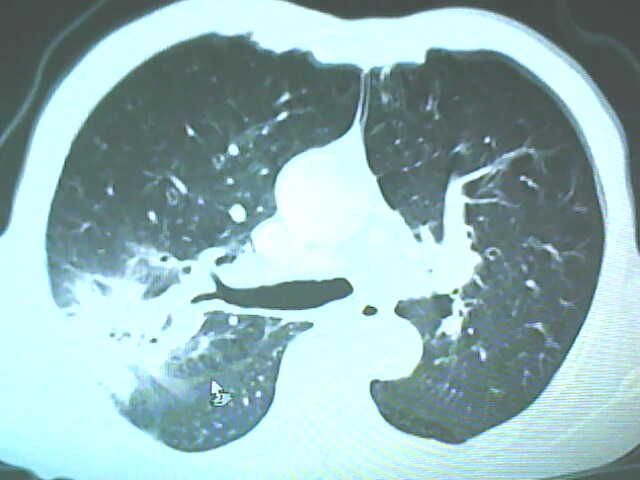

患者,男,66岁,以咳嗽、咳痰伴胸痛来就诊。

胸片提示右上肺占位病变。请各位老师看看ct。

请各位老师看看,考虑:癌性空洞吗?

考虑癌性空洞可能性大,空洞内壁不规则,病灶周围模糊,分叶、有毛刺

空洞内壁不规则,病灶周围模糊,分叶、毛刺呈日光放射状,突然截断,支持考虑癌性空洞

考虑右肺上叶后段周围型肺癌并癌性空洞形成。

考虑癌性空洞可能性大,内壁不规则,洞壁薄厚不均呈结节状突起,边缘模糊,分叶,毛刺

右上肺后段肺癌:

典型癌性空洞(偏心性,壁厚薄不均,内壁不光整),周围毛刺较僵硬,且有刺突征和血管聚集征